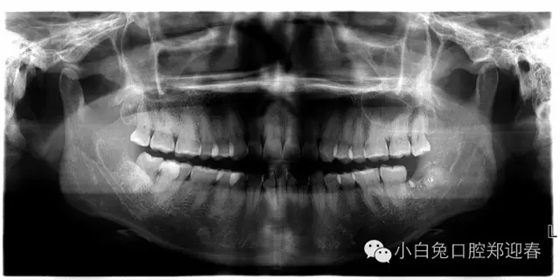

病例介紹:患者,女,37歲,要求拔除智齒斷根,1個半月前,因左下智齒拔除,術(shù)中因斷根取出未果而中斷拔牙,但術(shù)后一直不舒服,今來診要求拔除剩余一例智齒斷根二次拔除的感悟

術(shù)前片子

術(shù)后的全景片